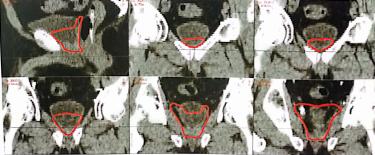

靶区勾画图示

A

B

C

A.耻骨联合以上水平横断面术后瘤床勾画;B.耻骨联合以下水平横断面术后瘤床勾画;C.矢状位和冠状位图像

图1-1 前列腺癌术后瘤床勾画注:1.上界一般在耻骨联合上3~4cm以内,包括输精管残端及前列腺瘤床。2.耻骨后方包全,侧界至闭孔内肌或肛提肌,后界至直肠前壁。3.下界勾画至膀胱尿道吻合口下8~12mm或尿道球上缘水平。